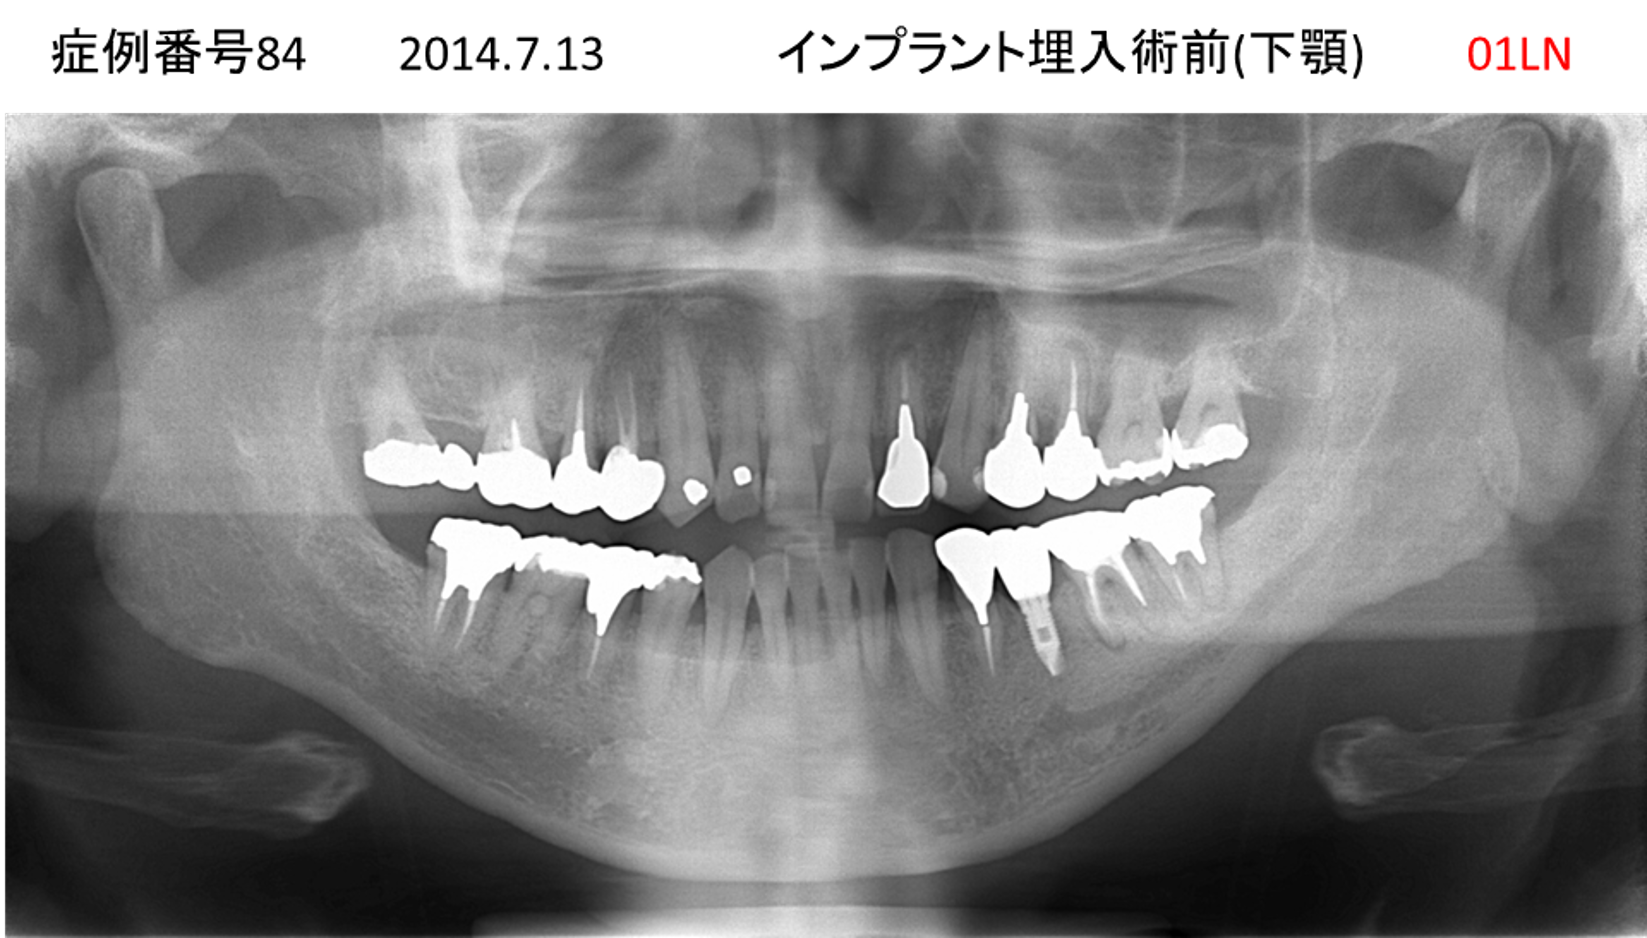

入れ歯が合わない患者様のインプラント症例

| 治療名称 |

インプラント |

| 治療費用 |

280万円+税 |

| 治療期間 |

4か月 |

| 患者さんの症状(主訴) |

入れ歯がもう無理。つらくてつけていられない。噛めない。 |

| 治療内容 |

| 治療結果 |

入れ歯と違って自分の歯みたい。とても快適。入れ歯と違って、しっかり噛める。 |

| 治療の注意点(リスク/副作用) |

インプラントが壊れたら再治療が必要 |